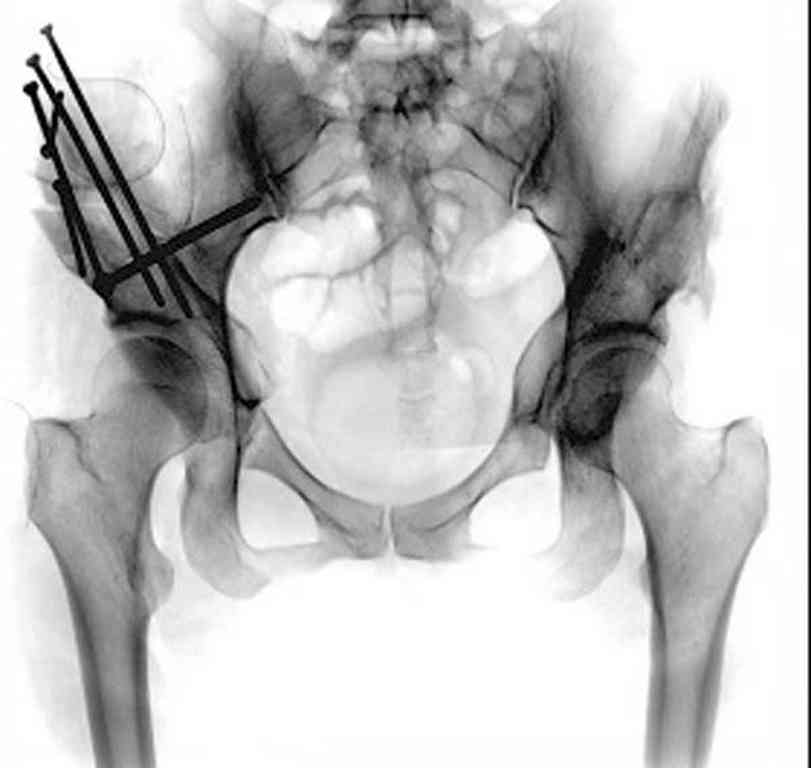

Представляю Р-снимки: обзорная, с отведением и с приведением.

Глубокоуважаемый Абдурашид. Здесь нет снимка с отведением. Если Вы сами сходили в рентгенкабинет и лично отвели пораженную конечность максимально возможно, а также дали максимально возможную внутреннюю ротацию-это одно!!!! Значит у пациентки тяжелейшая приводящая контрактура тазобедренного сустава!! И необходимо разобраться-миогенная или артрогенная? Если же Вы просто назначили указанный снимок и доверили произвести укладку рентгентехнику-это другое!!! Одному богу известно, что она делала, ведь на р-снимке отведения нет!

Все предыдущие корреспонденты предлагают вам достаточно простую вещь-смоделировать предлагаемую Вами операцию (т.е. дать отведение и внутреннюю ротацию) и посмотреть, как изменятся соотношения в суставе. Не обижайтесь, но судя по представлению клинического случая угловые величины, характеризующие пространственные соотношения в тазобедренном суставе, ваши рентгенологи не считают.

остеотомия таза по Хиари